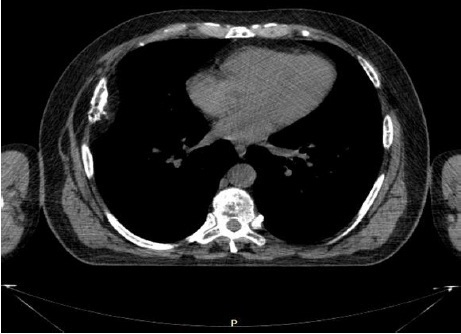

Мягкотканые образования в костях и мягких тканях выявлялись по данным компьютерной томографии (КТ) и магнитно-резонансной томографии (МРТ) (рис. 1–3). Эти инструментальные методы обследования позволили подтвердить наличие плазмоцитомы у данной категории больных (в костях грудной клетки, в позвоночнике, в глазнице).

Рис. 1. Разрушение кортикального слоя 6 ребра справа при компьютерной томографии грудной клетки